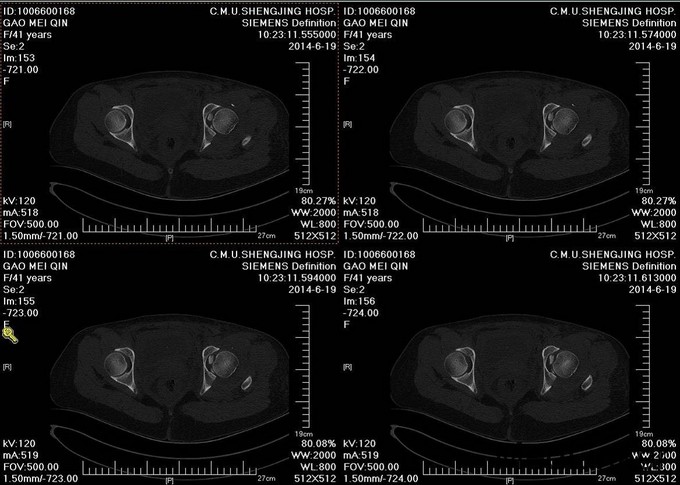

主诉:车祸外伤后左髋部疼痛伴活动受限4天 患者于2014年6月12日早6点左右被皮卡车撞伤,伤后患者出现一过性昏迷,被急诊送往当地医院,行DR及CT检查后,诊断为:左髋臼骨折,于当地医院骨科行骨牵引、抗炎补液等对症治疗后,现为求进一步治疗转入我科,患者病来无头晕头痛,无恶心呕吐,已排气排便.

入院后请神经外科会诊,请麻醉科会诊评估手术风险,查无明显手术禁忌症后,全麻下行左髋臼骨折切开复位内内固定术,术后留置引流,术后3天拔除引流管,切口换药无红肿渗出,术后4天转入当地医院继续治疗。

患者左髋臼骨折,髋臼骨折出血量大,应用自体血回输继续。术中注意血管及神经的副损伤。